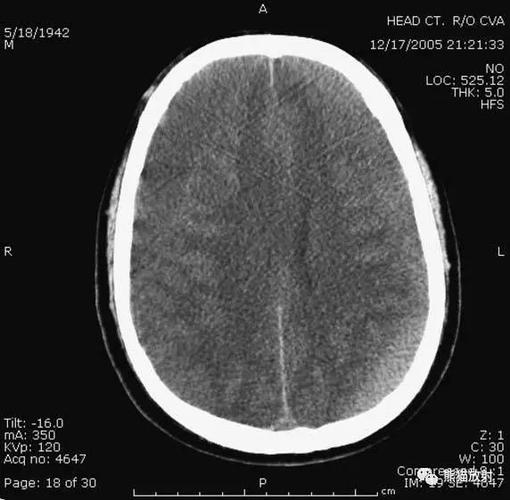

脑部ct报告单图片,正常的脑ct图片报告单

颅脑ct怎么看正常和异常影像分别是什么

脑出血的ct和mr分期及诊断

正常的脑ct图片报告单

脑部ct图片真实

正常人脑部ct高清图片

脑部ct图片

正常脑部ct图片

正常人脑部ct图片

脑部ct图片高清

正常脑ct图片